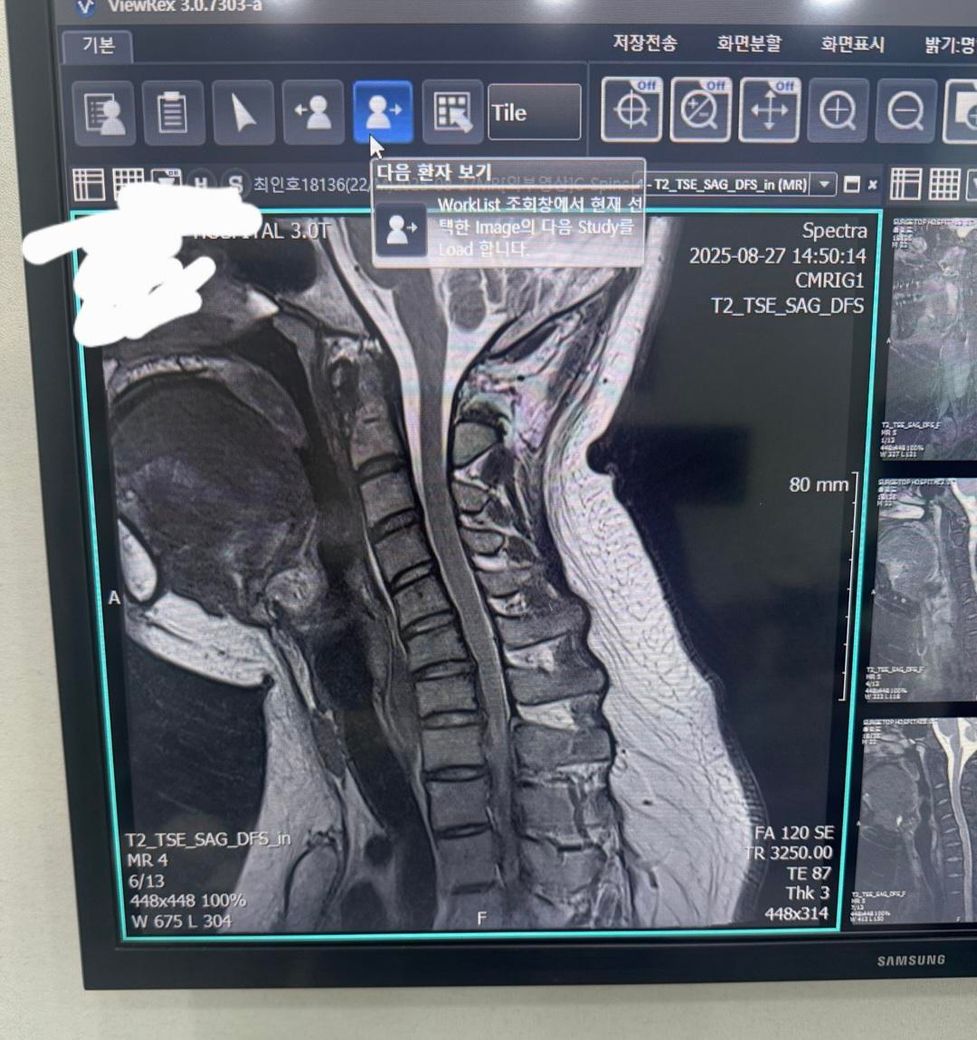

• 제시된 측면 X-ray와 시상면 MRI를 기준으로 보면, 경추 전만이 감소한 이른바 거북목 형태가 뚜렷하고, 하부 경추에서 디스크의 퇴행성 변화와 경미한 후방 돌출이 의심됩니다. MRI에서 척수는 연속성은 유지되며 뚜렷한 압박이나 신호 변화는 뚜렷하지 않아, 현재 단계는 “경추 정렬 이상 + 초기 디스크 퇴행/팽윤” 범주로 해석하는 것이 타당합니다. 즉 구조적 파열이나 심한 협착보다는, 자세와 근육 불균형에 의해 반복적으로 증상이 재발하는 상태에 가깝습니다.